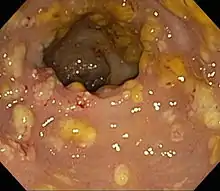

Prior to the advent of tests to detect C. difficile toxins, the diagnosis most often was made by colonoscopy or sigmoidoscopy. The appearance of "pseudomembranes" on the mucosa of the colon or rectum is highly suggestive, but not diagnostic of the condition.[45] The pseudomembranes are composed of an exudate made of inflammatory debris, white blood cells. Although colonoscopy and sigmoidoscopy are still employed, now stool testing for the presence of C. difficile toxins is frequently the first-line diagnostic approach. Usually, only two toxins are tested for—toxin A and toxin B—but the organism produces several others. This test is not 100% accurate, with a considerable false-negative rate even with repeat testing.[46]